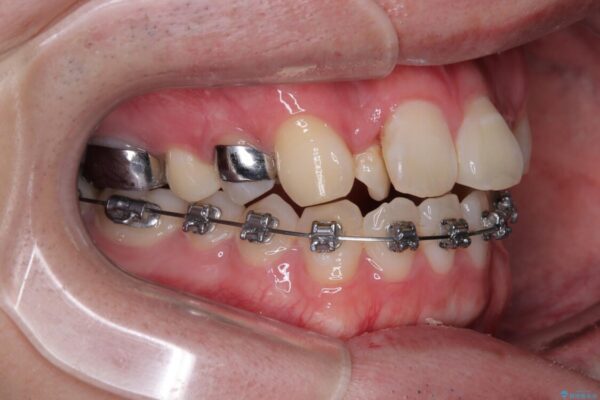

治療方針

このような歯列の狭さに起因するデコボコを改善するために、**MARPE(骨に固定する上顎急速拡大装置)**を使用して、上顎の横幅を拡大し、これにより歯が並ぶためのスペースを確保し、メタルブラケットを用いて歯列を整えていく計画としました。

費用面を考慮し、装置はコストパフォーマンスに優れたメタルブラケットを選択。見た目よりも機能と効果を重視したい方には特におすすめの選択肢です。

治療途中

• 1年でここまで変わる!歯列のがたつきと正中のズレを改善した矯正治療(メタルブラケット×MARPE) 治療途中画像